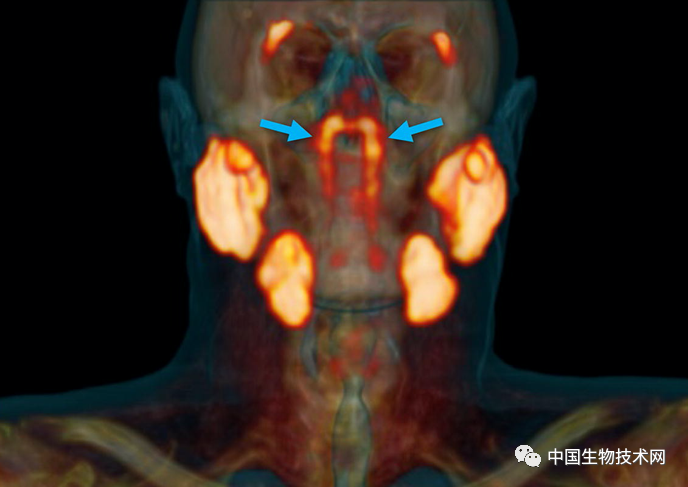

这个“未知实体”是该团队在对100例前列腺癌或尿道腺癌患者进行回顾性队列检查,以评估PSMA PET/CT(前列腺特异性膜抗原正电子发射型计算机断层显像)阳性区域的存在和形态时偶然发现的。与放射性葡萄糖注射液搭配使用时,该诊断工具可以突出显示体内肿瘤。

在对所有100例患者进行的PSMA PET/CT扫描,均发现存在这些管腺,并且对两名尸体(一男一女)的身体检查也显示出神秘的双侧结构,从宏观上可见引流管开口朝向鼻咽壁。

至于这些腺体是如何被识别出来的,研究人员表示,“管状腺”是在颅底一个不易接近的解剖位置被发现的,用内窥镜是很难辨认出来的,因为它们是一个更大腺体系统的一部分。此外,只有更新的PSMA-PET/CT成像技术才能检测到新唾液腺的结构,这超出了超声波、CT和MRI扫描等技术的可视化能力。